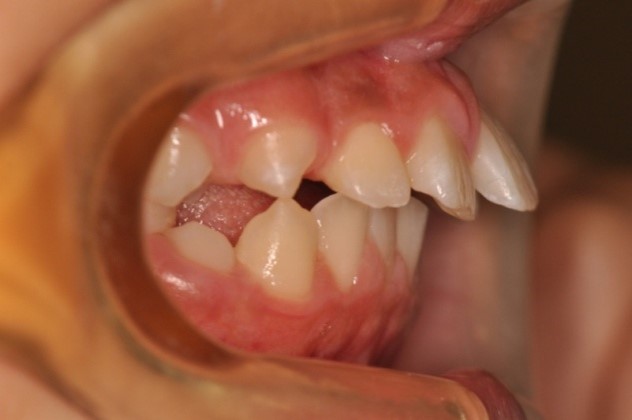

こちらは、お口の中を横から見たときの写真です。

の方に比べ、の方は上の歯がでているのが、見てわかると思います。